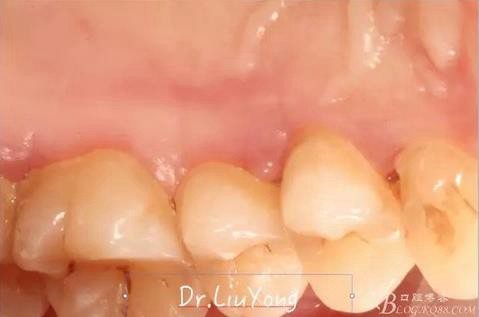

檢查:面部對(duì)稱無(wú)腫脹畸形,張口度正常,口內(nèi)檢查可見A2牙冠缺失,可見直徑約1.5mm左右穿髓孔,冷熱刺激痛+,叩痛+,探痛+,近中斷面探診位于齦下1.5mm,A1B1B2松動(dòng)2-3度,B1牙冠缺失1/2,冷熱刺激痛-,叩痛+,B2牙冠完整,A2-B2牙齦紅腫,探診極易出血,全口口腔衛(wèi)生差,牙結(jié)石++,A1B1之間牙齦乳頭紅腫嚴(yán)重,B1唇側(cè)牙齦萎縮明顯,牙齦邊緣可見縫線兩處,局部有滲出,齦緣冠方1mm處見白色骨塊,松動(dòng),觸痛明顯,觸及骨塊時(shí)可見B1及B2近中唇側(cè)牙齦動(dòng)度,B1B2之間唇側(cè)牙齦乳頭缺失,B2近中根面可見大量牙結(jié)石。重度深覆合,牙尖交錯(cuò)位時(shí)C3-D2咬至上前牙腭側(cè)齦緣,A1切端咬至C12唇側(cè)齦緣。其余牙齒未見明顯異常。

術(shù)前口內(nèi)照片如下: